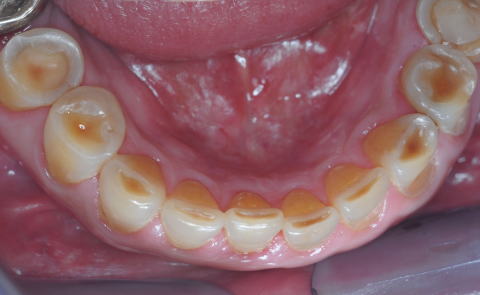

■症例1−3 酸蝕症 Acid Erosion

前歯切端と臼歯部咬合面に診られる広範囲のEnamel質欠損

■症例1−2 酸蝕症 Acid Erosion

前歯舌面と臼歯咬合面のEnamel質が消失。当然咬合高径が低くなり、過蓋咬合になる。研磨剤入りの歯磨剤がEnamel質消失を加速した